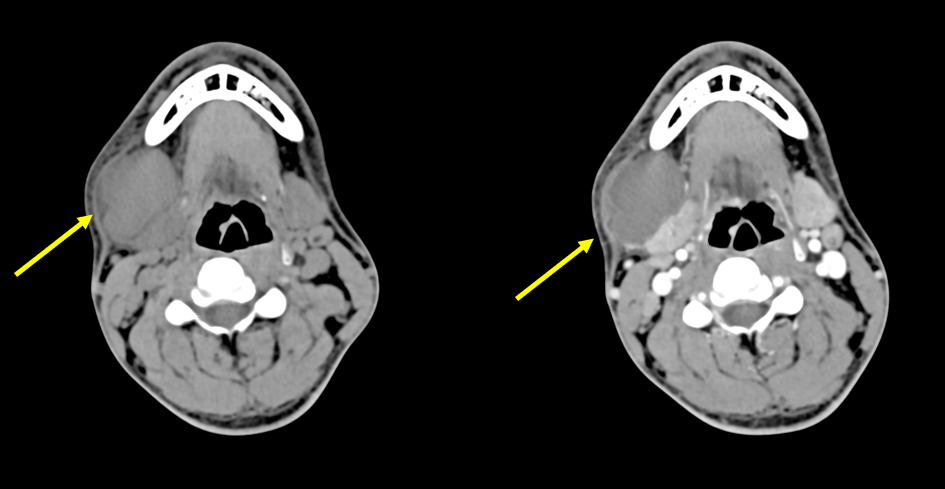

• 右頸部に多発する嚢胞性(または壊死性)病変、リンパ節腫大

1年前顎下腺腫瘍疑いとして右顎下部郭清術施行。病理所見としては膿瘍の診断であるが、特定の感染症を示唆する所見を認めず(詳細不明)。腫瘍は認めず、その後症状は落ち着いていた。

組織学的には、割面にて20mm大の膿瘍形成を認める。壊死に陥った領域も広く認められる。膿瘍周囲には線維化やリンパ球浸潤を伴っている。悪性所見は認めない。

【1年前の画像】

新たに左頸部にリンパ節腫大出現膿瘍壊死のみ